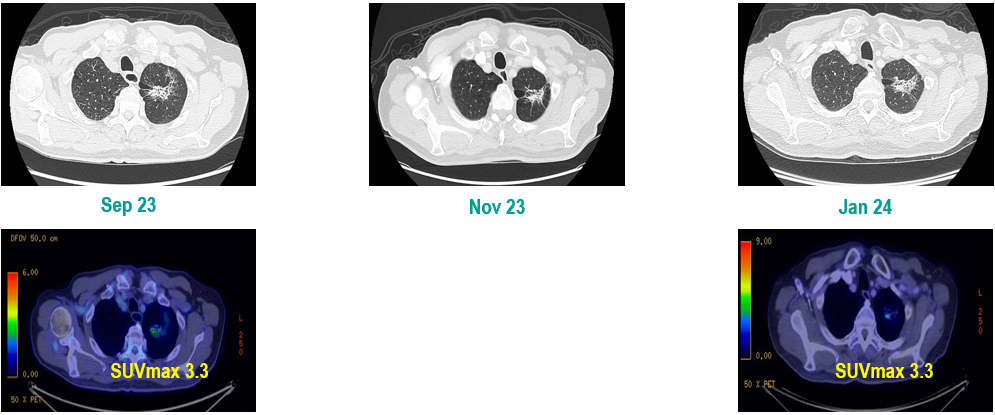

PET-CT(2023年9月):右下肺叶发现6.9×6.7×6.6cm的FDG高摄取肿块,伴右侧第7、8肋骨侵犯可疑,右肺门淋巴结肿大,双肺上叶多发结节,考虑腺癌谱系疾病。

CT及PET-CT随访(2023年11月、2024年1月):评估新辅助治疗效果,右下肺叶肿块缩小,右肺门淋巴结代谢活性消失,右肺上叶结节稳定但代谢活性降低,左肺上叶及双侧磨玻璃样病变稳定。

新辅助治疗:患者接受4周期新辅助化疗联合免疫治疗(培美曲塞、顺铂、纳武利尤单抗),治疗后影像学显示肿块缩小,代谢活性降低。